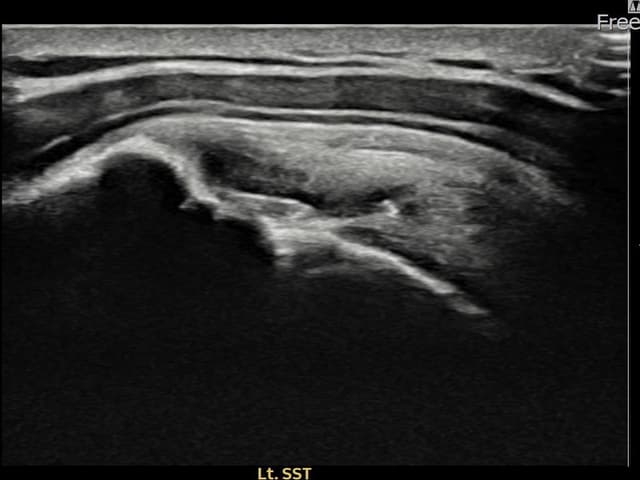

左侧 冈上肌腱 石灰化肌腱炎

16mm × 11mm